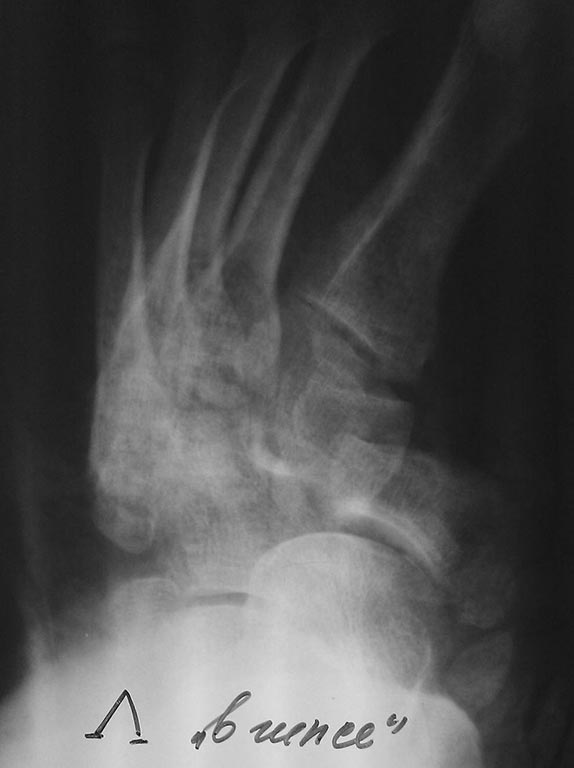

А что за механизм травмы? И почему Вы сконцентрировались только на ладье? Мне кажется, для того, чтобы составить план лечения в такой сложной ситуации, нужно хотя бы сформулировать диагноз. Очень похоже, что поврежден и сустав Лмсфранка, есть переломовывихи других костей, к которым удобнее добираться через тыльные доступы. Без КТ разобраться и составить четкий план очень сложно. Возможно, если бы сразу сделали КТ, не стали бы так перерастягивать стопу и не спровоцировали некроз мягких тканей. Да и смещение тут больше боковое, чем по длине. Так что, вполне можно демонтировать аппарат, чтобы на фоне некроза не развилась глубокая инфекция, сделать КТ и, имея полную информацию, планировать вмешательство.

С Лисфранком проблемы проекционные (разглядывали под ЭОПом). Уверены, что сразу залезть открыто через 2,5 мес при такой картинке было бы более безопасно? Подобный дистрактор уже использовали, сильно облегчает операцию, уменьшает травматичность, проблем не было.

Ужасно. И это относится не только к снимкам. Не поленитесь, все-таки, сделать КТ, чтобы увидеть реальный объем повреждений и реальную ситуацию после операции.

Как можно подсказать то, чего не видишь? Я и подсказал, что нужно КТ. Ведь чтобы оперировать необходим хотя бы полный диагноз. А его не было. И по представленным рентгенограммам определить полный объем повреждений было невозможно.